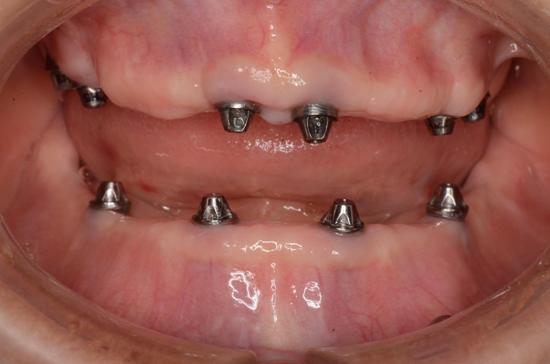

All-on-Fou/Six

近年來由於人工植牙的技術普及,患者大都知道植牙可做固定式假牙,但同樣的有時患者因為身體、經劑因素等受限,也可以考慮植入幾支人工植牙,再完成固定可撤式活動義齒,這樣可讓活動式假牙的固定性有效加強。通常上顎可用6支植體,下顎則4-5支植體固定,如需更穩定的受力,亦可再增加植體數目。(圖52-55)